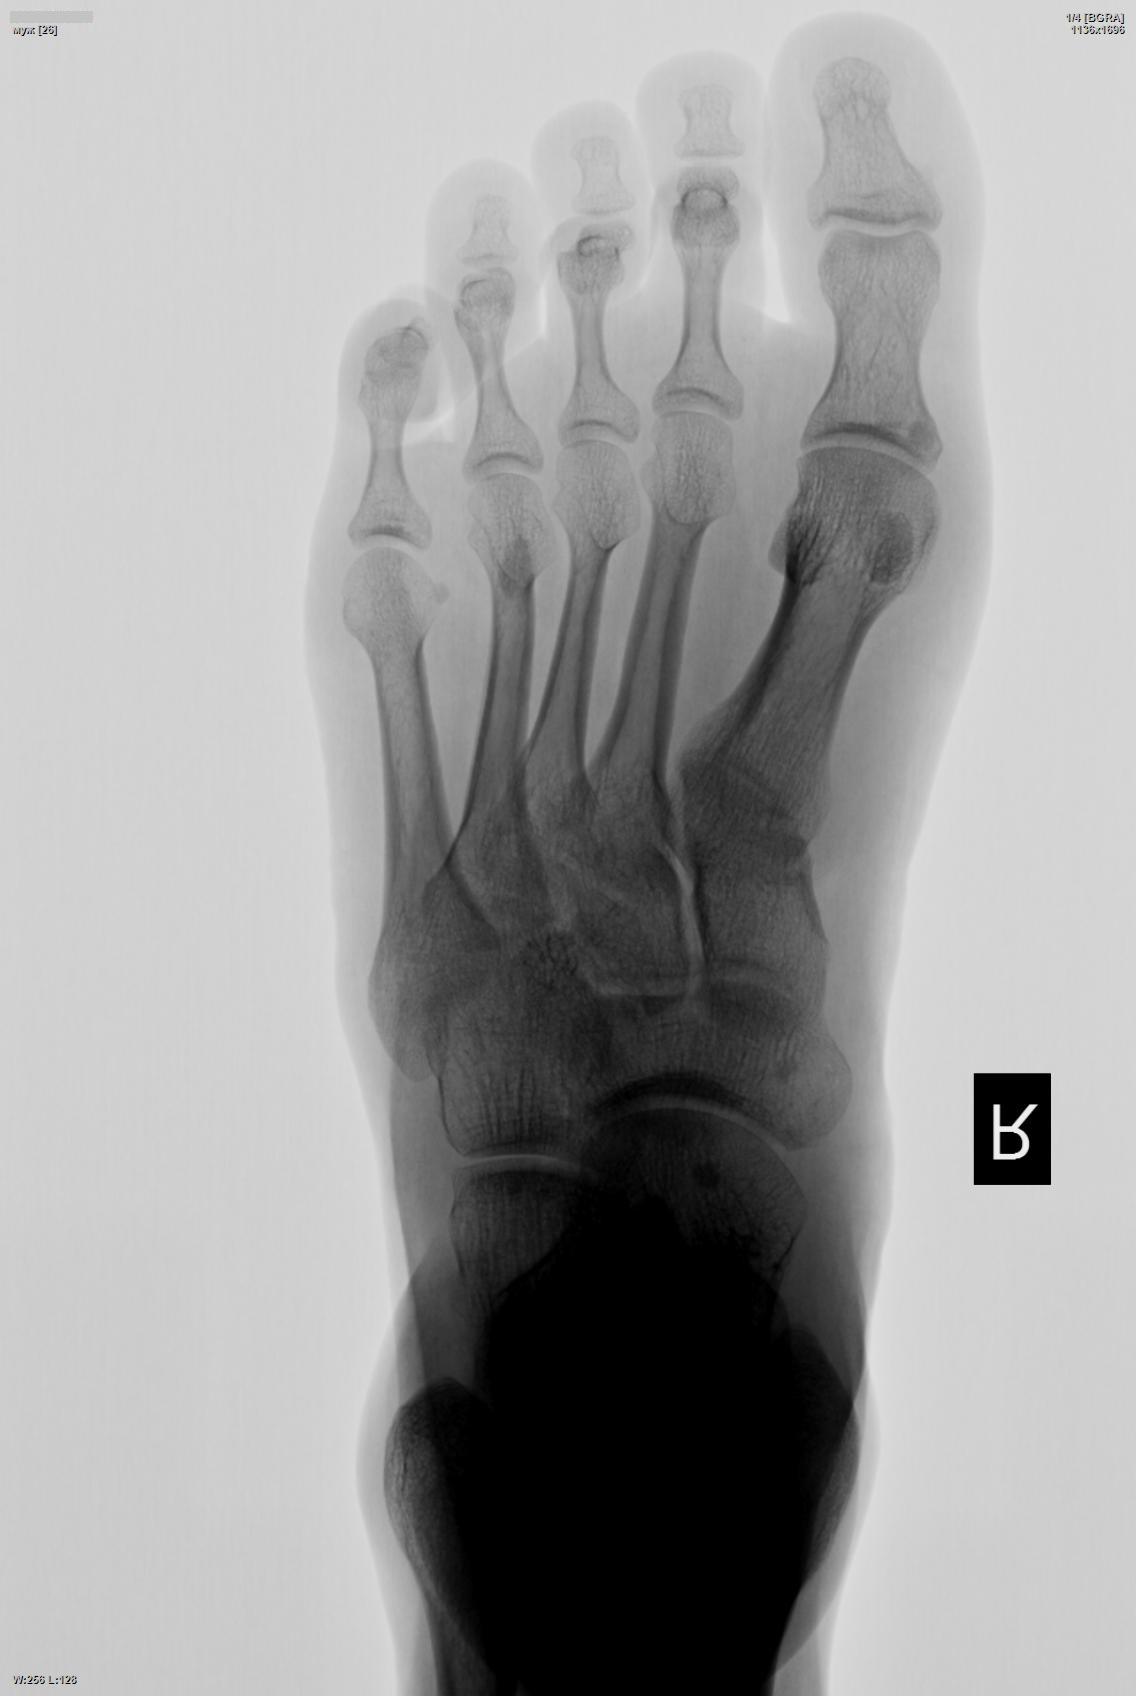

Интересные уплотнения.

Эностоз или остеопойкилия?

Похоже , кажется, на случай shlyapa с бедренной костью, интересно, есть у этого научное название ? Может, Андрей Юрьевич заглянет сюда...

А это и есть ответ.